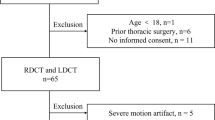

Patients who underwent vascular dynamic CT examination including the chest (unenhanced, arterial phase, and delayed phase) from January 2021 to February 2023 were included in this study. The following patients were excluded: (a) error in automatic segmentation of the lung or bronchus (n = 3) and (b) lost data regarding contrast material (n = 1). The patient inclusion and exclusion processes are illustrated in Fig. 1.